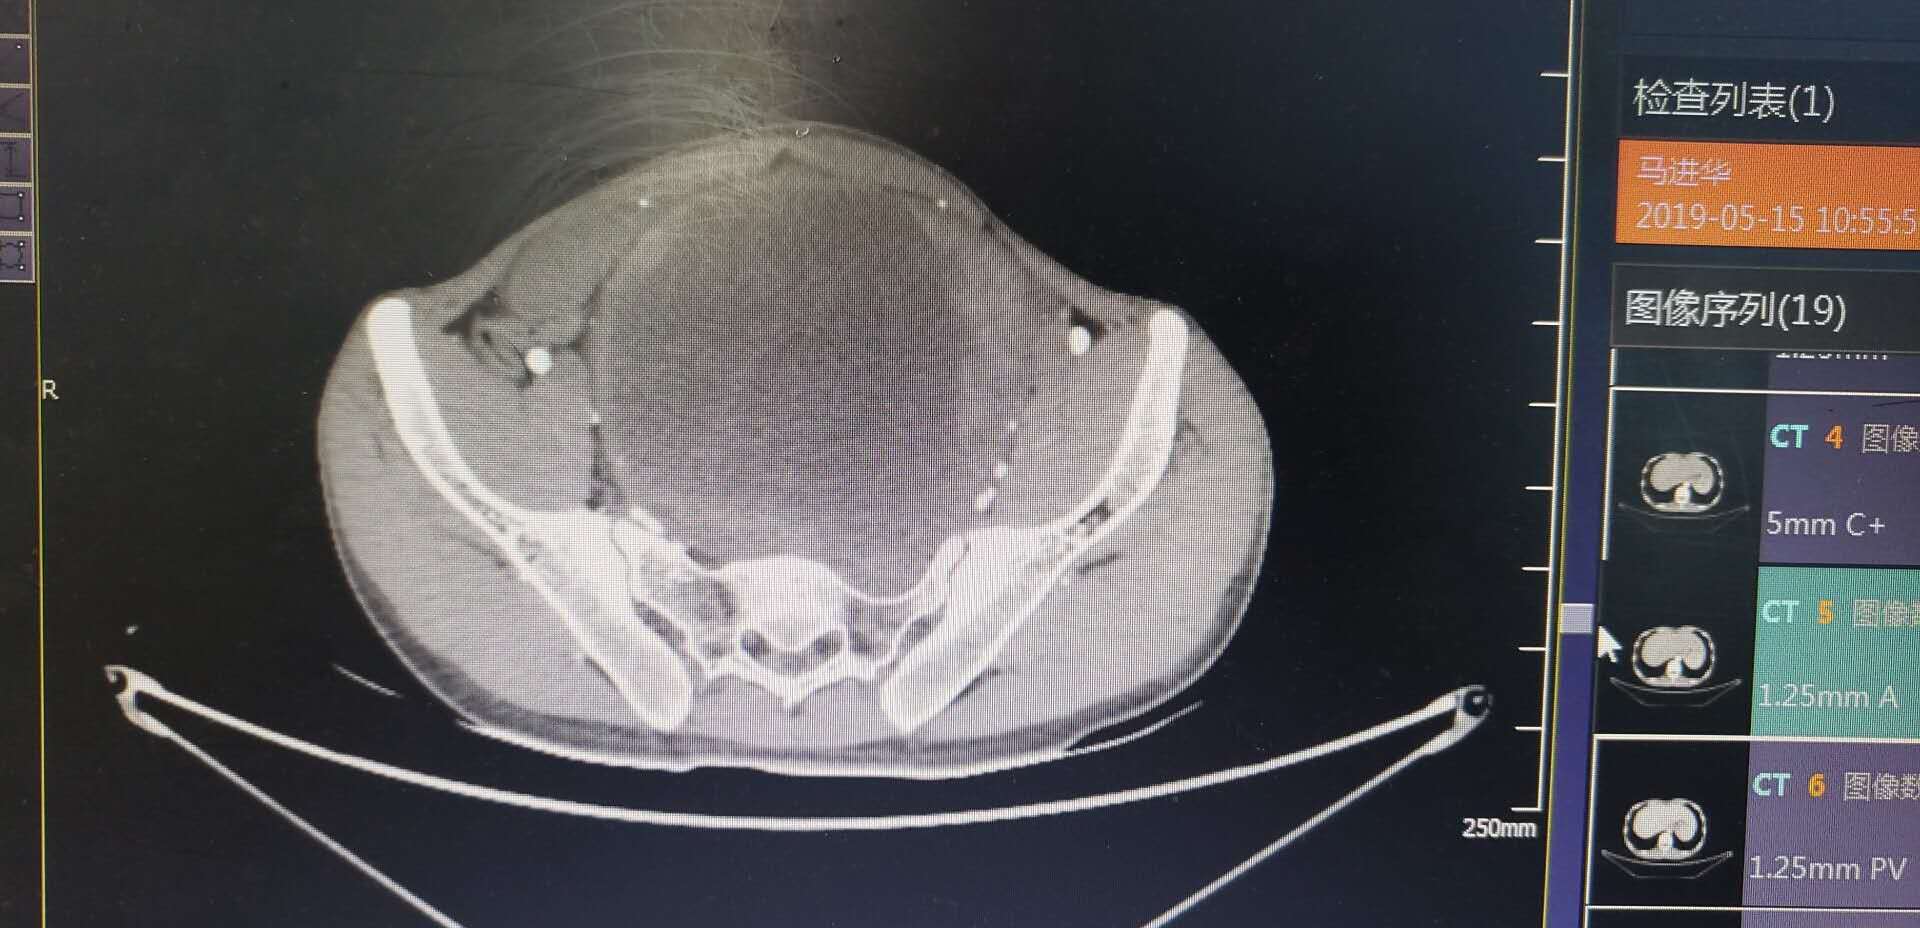

该患者罹患腹膜后肿瘤,压迫输尿管、膀胱、直肠、血管等重要脏器组织,引起相应的功能障碍,手术难度非常大。且该患者家庭条件也较困难,失去劳动力的家庭难以负担治疗费用,但医者不愿意放弃任何渴望生存的希望。最终,在陈昊主任医师团队的精心准备及规划下,经过肿瘤外科、麻醉科、泌尿外科、血管外科等通力合作,完整地切除了肿瘤,保存了所有受侵犯的器官组织,成功完成了该例手术,赋予了该患者新的生命。